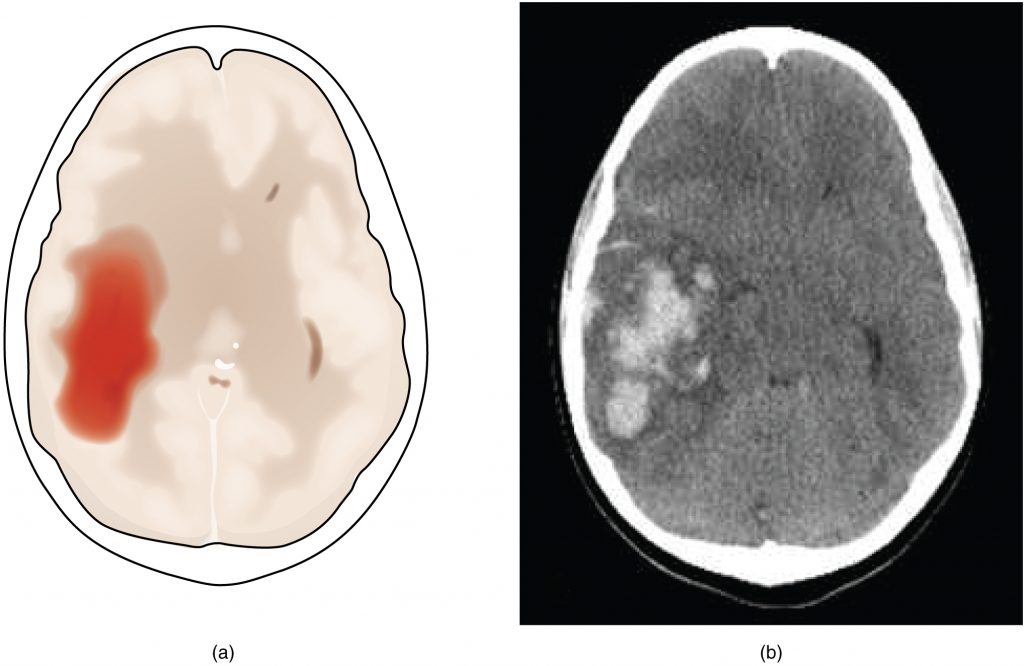

A hemorrhagic stroke is bleeding into the brain because of a damaged blood vessel. Accumulated blood fills a region of the cranial vault and presses against the tissue in the brain (Figure 2.3). Physical pressure on the brain can cause the loss of function, as well as the squeezing of local arteries resulting in compromised blood flow beyond the site of the hemorrhage. As blood pools in the nervous tissue and the vasculature is damaged, the blood-brain barrier can break down and allow additional fluid to accumulate in the region, which is known as edema.

Hemorrhagic Stroke

Figure 2.3 – Hemorrhagic Stroke: (a) A hemorrhage into the tissue of the cerebrum results in a large accumulation of blood with an additional edema in the adjacent tissue. The hemorrhagic area causes the entire brain to be disfigured as suggested here by the lateral ventricles being squeezed into the opposite hemisphere. (b) A CT scan shows an intraparenchymal hemorrhage within the parietal lobe. (credit b: James Heilman)